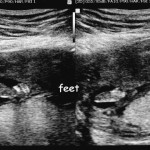

Categories events It’s a Girl! 16 Week Ultrasounds Post author By sean Post date September 7, 2012 Second set of ultrasounds, to help narrow the due date. At an estimated 16 weeks, we now know we are going to have a girl! Tags girl, ultrasounds